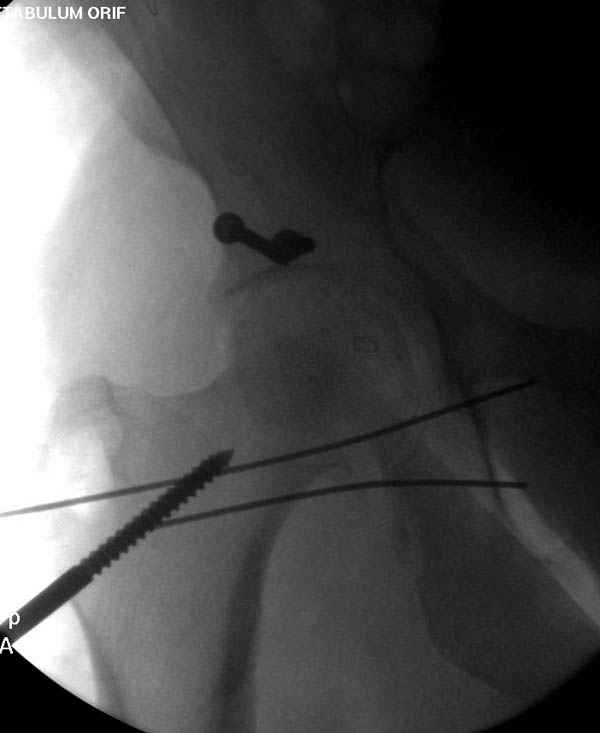

Второй случай, для лечения перелома проксимального

плеча применили пластину "Hand Innovation"

http://www.handinnovations.com/pdf/S3_technique.pdf

Пластина имеет преимущества перед другими "Locking

Implants", потому что пластину можно уложить намного ниже чем другие пластины и имеется возможности проведения шурупов под 130 градусным углом, таким образом можно уменьшить операционный разрез в проксимальной части.

Прооперирован вчера на 13 день после поступления.

Больному 41 и из-за гемодинамической нестабильности в течение первых 7 дней был в реанимации под интубационной седацией.

Кроме перелома плеча у больного старый дистракционный перелом T12-L1 оперированный когда-то и кем-то, открытый перелом костей предплечья, который был прооперирован в ночь поступления, после I&D (хирургической обработки). Из-за разрыва селезенки при поступлении травма хирургами произведено удаление.

Дополнительно имеется перелом ацетабулума: задняя

колонна с полупоперечным переломом, и переломы костей лица.

На седьмой день зафиксирован перелом ацетабулума через задний доступ. Перед операцией для профилактики DVT, IVC фильтер, также получает Lovenox.

После операции на ацетабулум был экстубирован, сегодня опять же интубирован, из-за невменяемости и казуса, проявления "вампирства" - опустошил посуду с кровью от дренажа.

Извиняюсь за качества снимков, обычный больной в 300 фунтов, портативным ренген аппаратом не пробить.